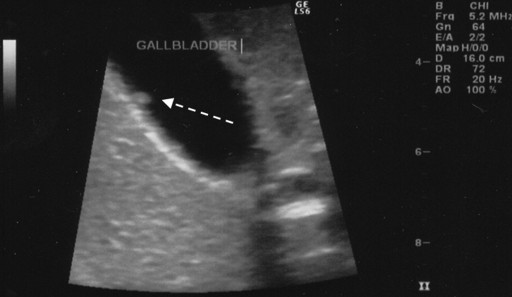

Furthermore, examination of the other systems did not disclose pathological findings. The patient’s temperature was 37.2°C. Laboratory data other than amylasuria (1,030 IU/L; reference range: 0-500 IU/L) were within the reference limits. The ultrasonographic study showed a small well-defined, non-mobile echogenic structure of 4 mm in diameter attached to the wall of the gallbladder. The features of the echogenic structure were suggestive of a gallbladder polyp (Figure 1) but not of a gallstone. Therefore, the most likely diagnosis was a gallbladder polyp and a laparoscopic cholecystectomy was carried out.

|

Figure 1. An echogenic non-mobile structure attached to the gallbladder wall: features suggestive of a polyp. |